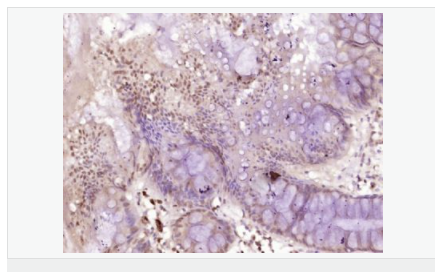

| 產(chǎn)品應(yīng)用 | WB=1:500-2000 ELISA=1:5000-10000 IHC-P=1:100-500 IHC-F=1:100-500 IF=1:100-500 (石蠟切片需做抗原修復(fù)) not yet tested in other applications. optimal dilutions/concentrations should be determined by the end user. |

| 細胞定位 | 細胞核 |